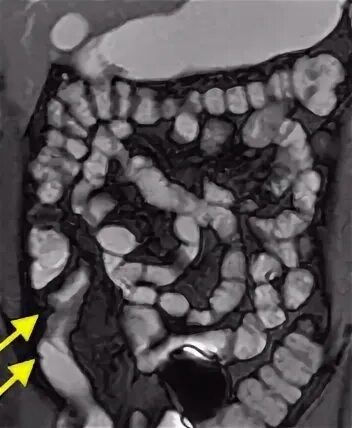

Энтерография сделать